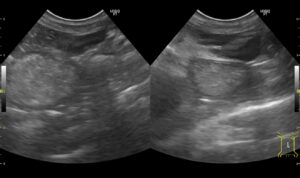

- 画像検査

レントゲンやエコー検査を実施

消化管の肥厚や消化管リンパ節の腫大を認めることが多い